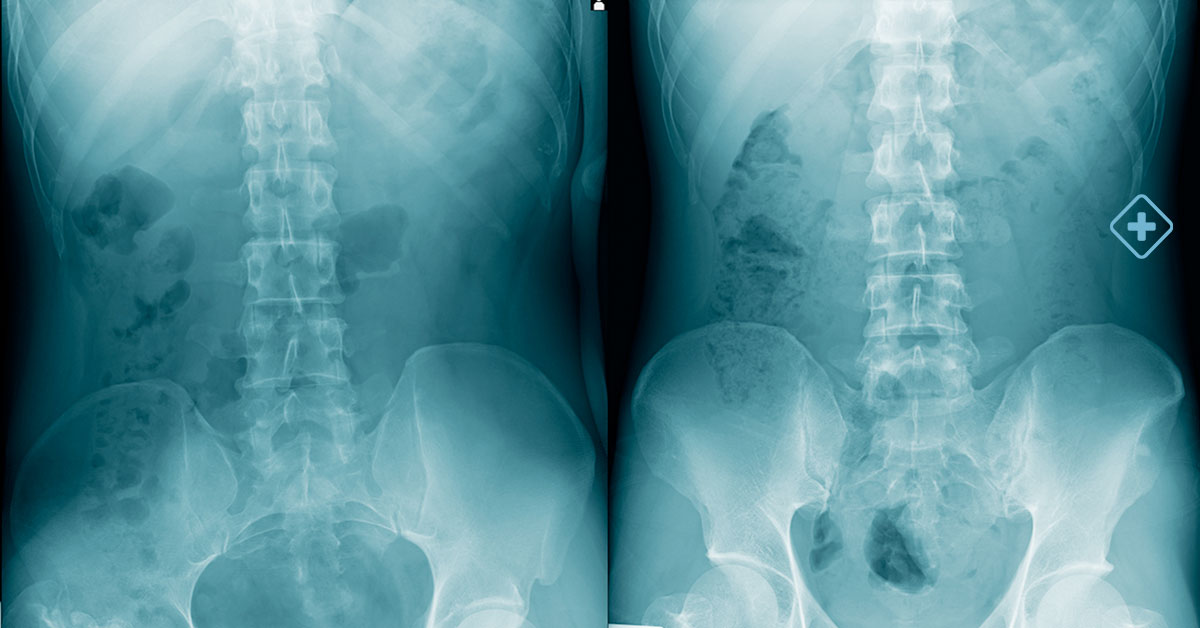

This may include advanced diagnostic tests, such as MRIs, CT scans, and X-rays, which will help the specialists fully understand the nature and extent of the problem.